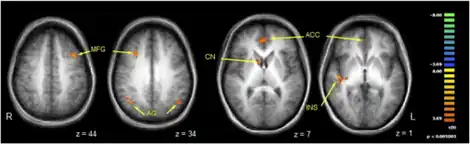

There has been much recent interest in using functional neuroimaging to study conversion. As researchers identify the mechanisms which underlie conversion symptoms, it is hoped they will enable the development of a neuropsychological model. A number of such studies have been performed, including some which suggest the blood-flow in patients' brains may be abnormal while they are unwell. However, the studies have all been too small to be confident of the generalisability of their findings, so no neuropsychological model has been clearly established.